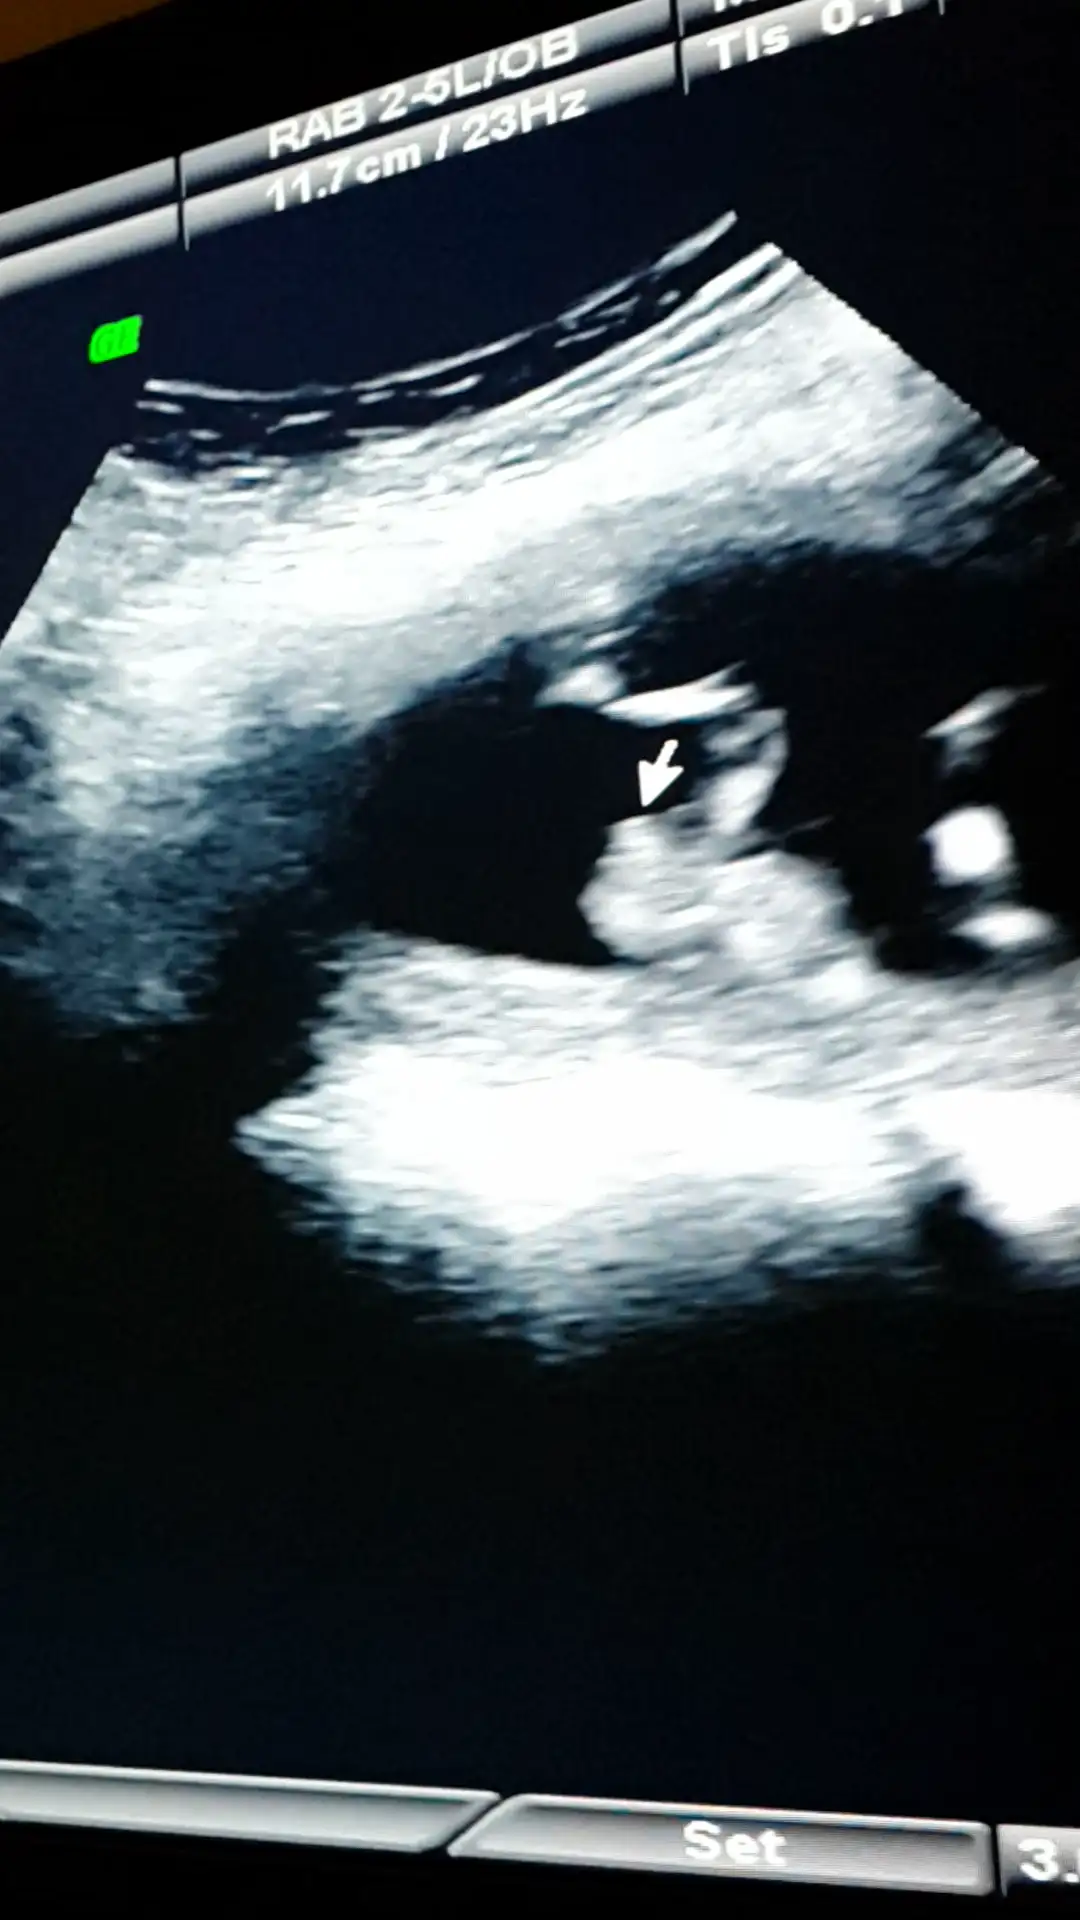

Ustteki fotoda erkek gibi eger kordon degilse digerlerinde kiz gibi doktor bisey dedimi

Canim esim bebisi videoya cekmisti ordan kopyaladigim bir resmi ekledim doktorun tam cikintisini isaretleyip gosterdigi yerin resmi. Onuda paylasmak istedim bi bakarsin tekrar doktorla ayni fikirdemisiniz merak ettim senin yorumunuda :anneadayı: